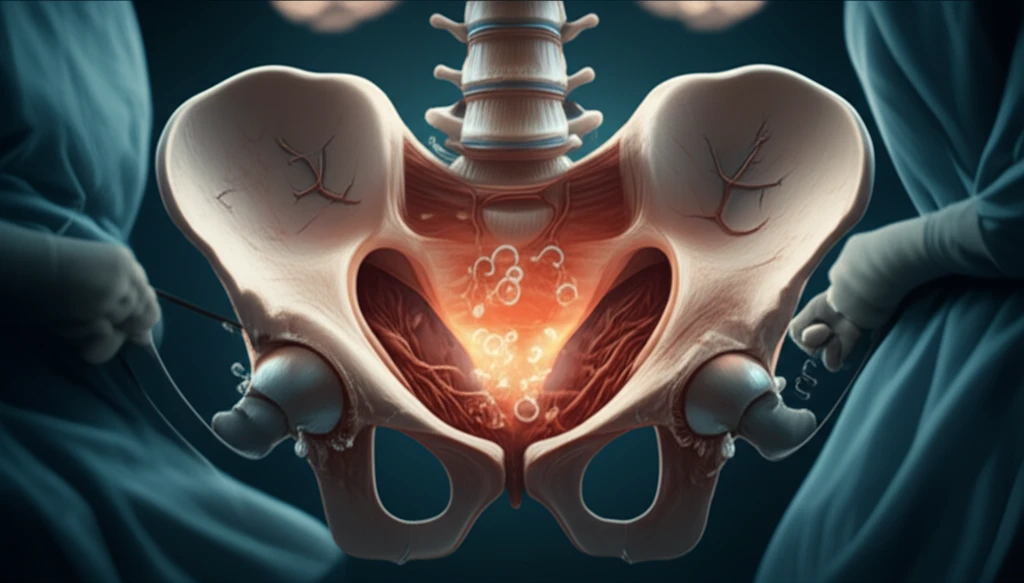

Transanal Total Mesorectal Excision (taTME) has revolutionized colorectal surgery, offering new hope for patients needing complex procedures. However, with any innovative technique comes a learning curve and the potential for unexpected complications. One such concern is carbon dioxide (CO2) embolism, a rare but serious event that can occur during the transanal phase of taTME.

The exact cause of CO2 embolism during taTME is likely multifactorial, involving a combination of factors that create a perfect storm. Let's break down the key elements that can contribute to this complication:

- Pneumo-pelvis Pressure: The pressure within the pneumo-pelvis can prevent small veins from collapsing completely when cut.

- AirSEAL® and Suction: The use of AirSEAL® for insufflation, combined with liberal suction, can create rapid changes in flow rates, promoting turbulent CO2 flow and increasing the likelihood of embolism.